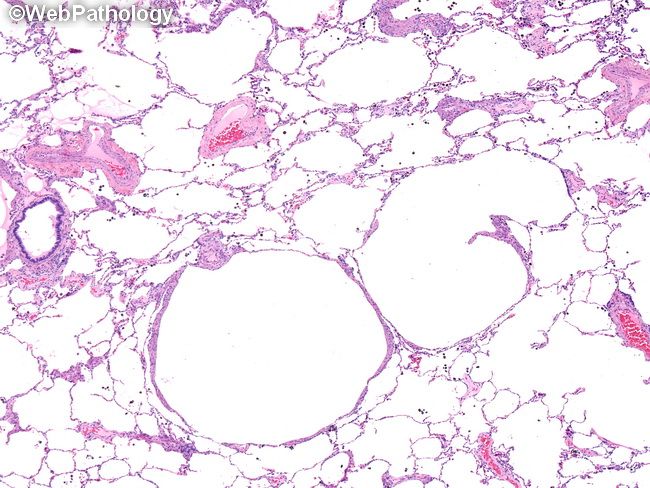

Лам клетки

Лам клетки 82 фото